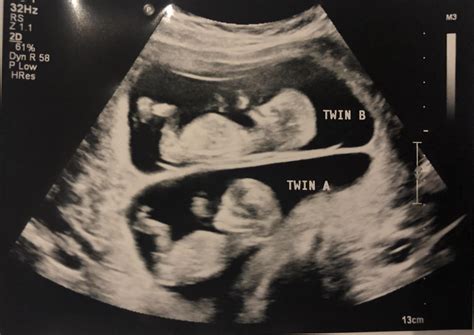

A 36 weeks pregnant sonogram is typically performed to evaluate the baby's growth, position, and overall health. At this stage, the baby is almost fully developed, and the ultrasound can provide valuable information about the baby's readiness for birth. The sonogram at 36 weeks is often more detailed than earlier scans, offering a clearer picture of the baby's anatomy and any potential issues that may need to be addressed before delivery.

The technician will also check the baby's position in the uterus, which is crucial for planning the delivery. If the baby is in a breech position (feet or buttocks down), the healthcare provider may discuss options for turning the baby or planning a cesarean section.

This scan is particularly important for identifying any potential complications that may arise during labor and delivery. For example, if the baby is in a breech position, the healthcare provider may recommend an external cephalic version (ECV) to turn the baby into a head-down position. If the baby is too large or too small, the provider may need to adjust the delivery plan accordingly.

During the 36 weeks pregnant sonogram, several common findings may be noted. These findings can help healthcare providers assess the baby's health and plan for delivery. Some of the most common findings include:

• Fetal movement: The baby should be active and moving regularly.

• Fetal heart rate: The baby's heart rate should be within the normal range (120-160 beats per minute).

• Fetal position: The baby should be in a head-down position, ready for delivery.

• Amniotic fluid levels: There should be an adequate amount of amniotic fluid surrounding the baby.

• Placental position: The placenta should be in a healthy position and not covering the cervix.